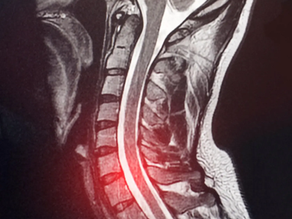

Exploring Sacro Occipital Technique Pelvic Block Treatment for Herniated Discs: A Case Study Review

Lumbar disc herniation causes significant pain and mobility issues for many patients. While surgery is often considered, conservative chiropractic care offers promising alternatives. This post reviews a case study by Blum C, presented in the Journal of Chiropractic Education (2004), which highlights the use of Sacro Occipital Technique (SOT) pelvic block treatment for severe herniated discs. The study provides insight into how this method can reduce pain and improve function